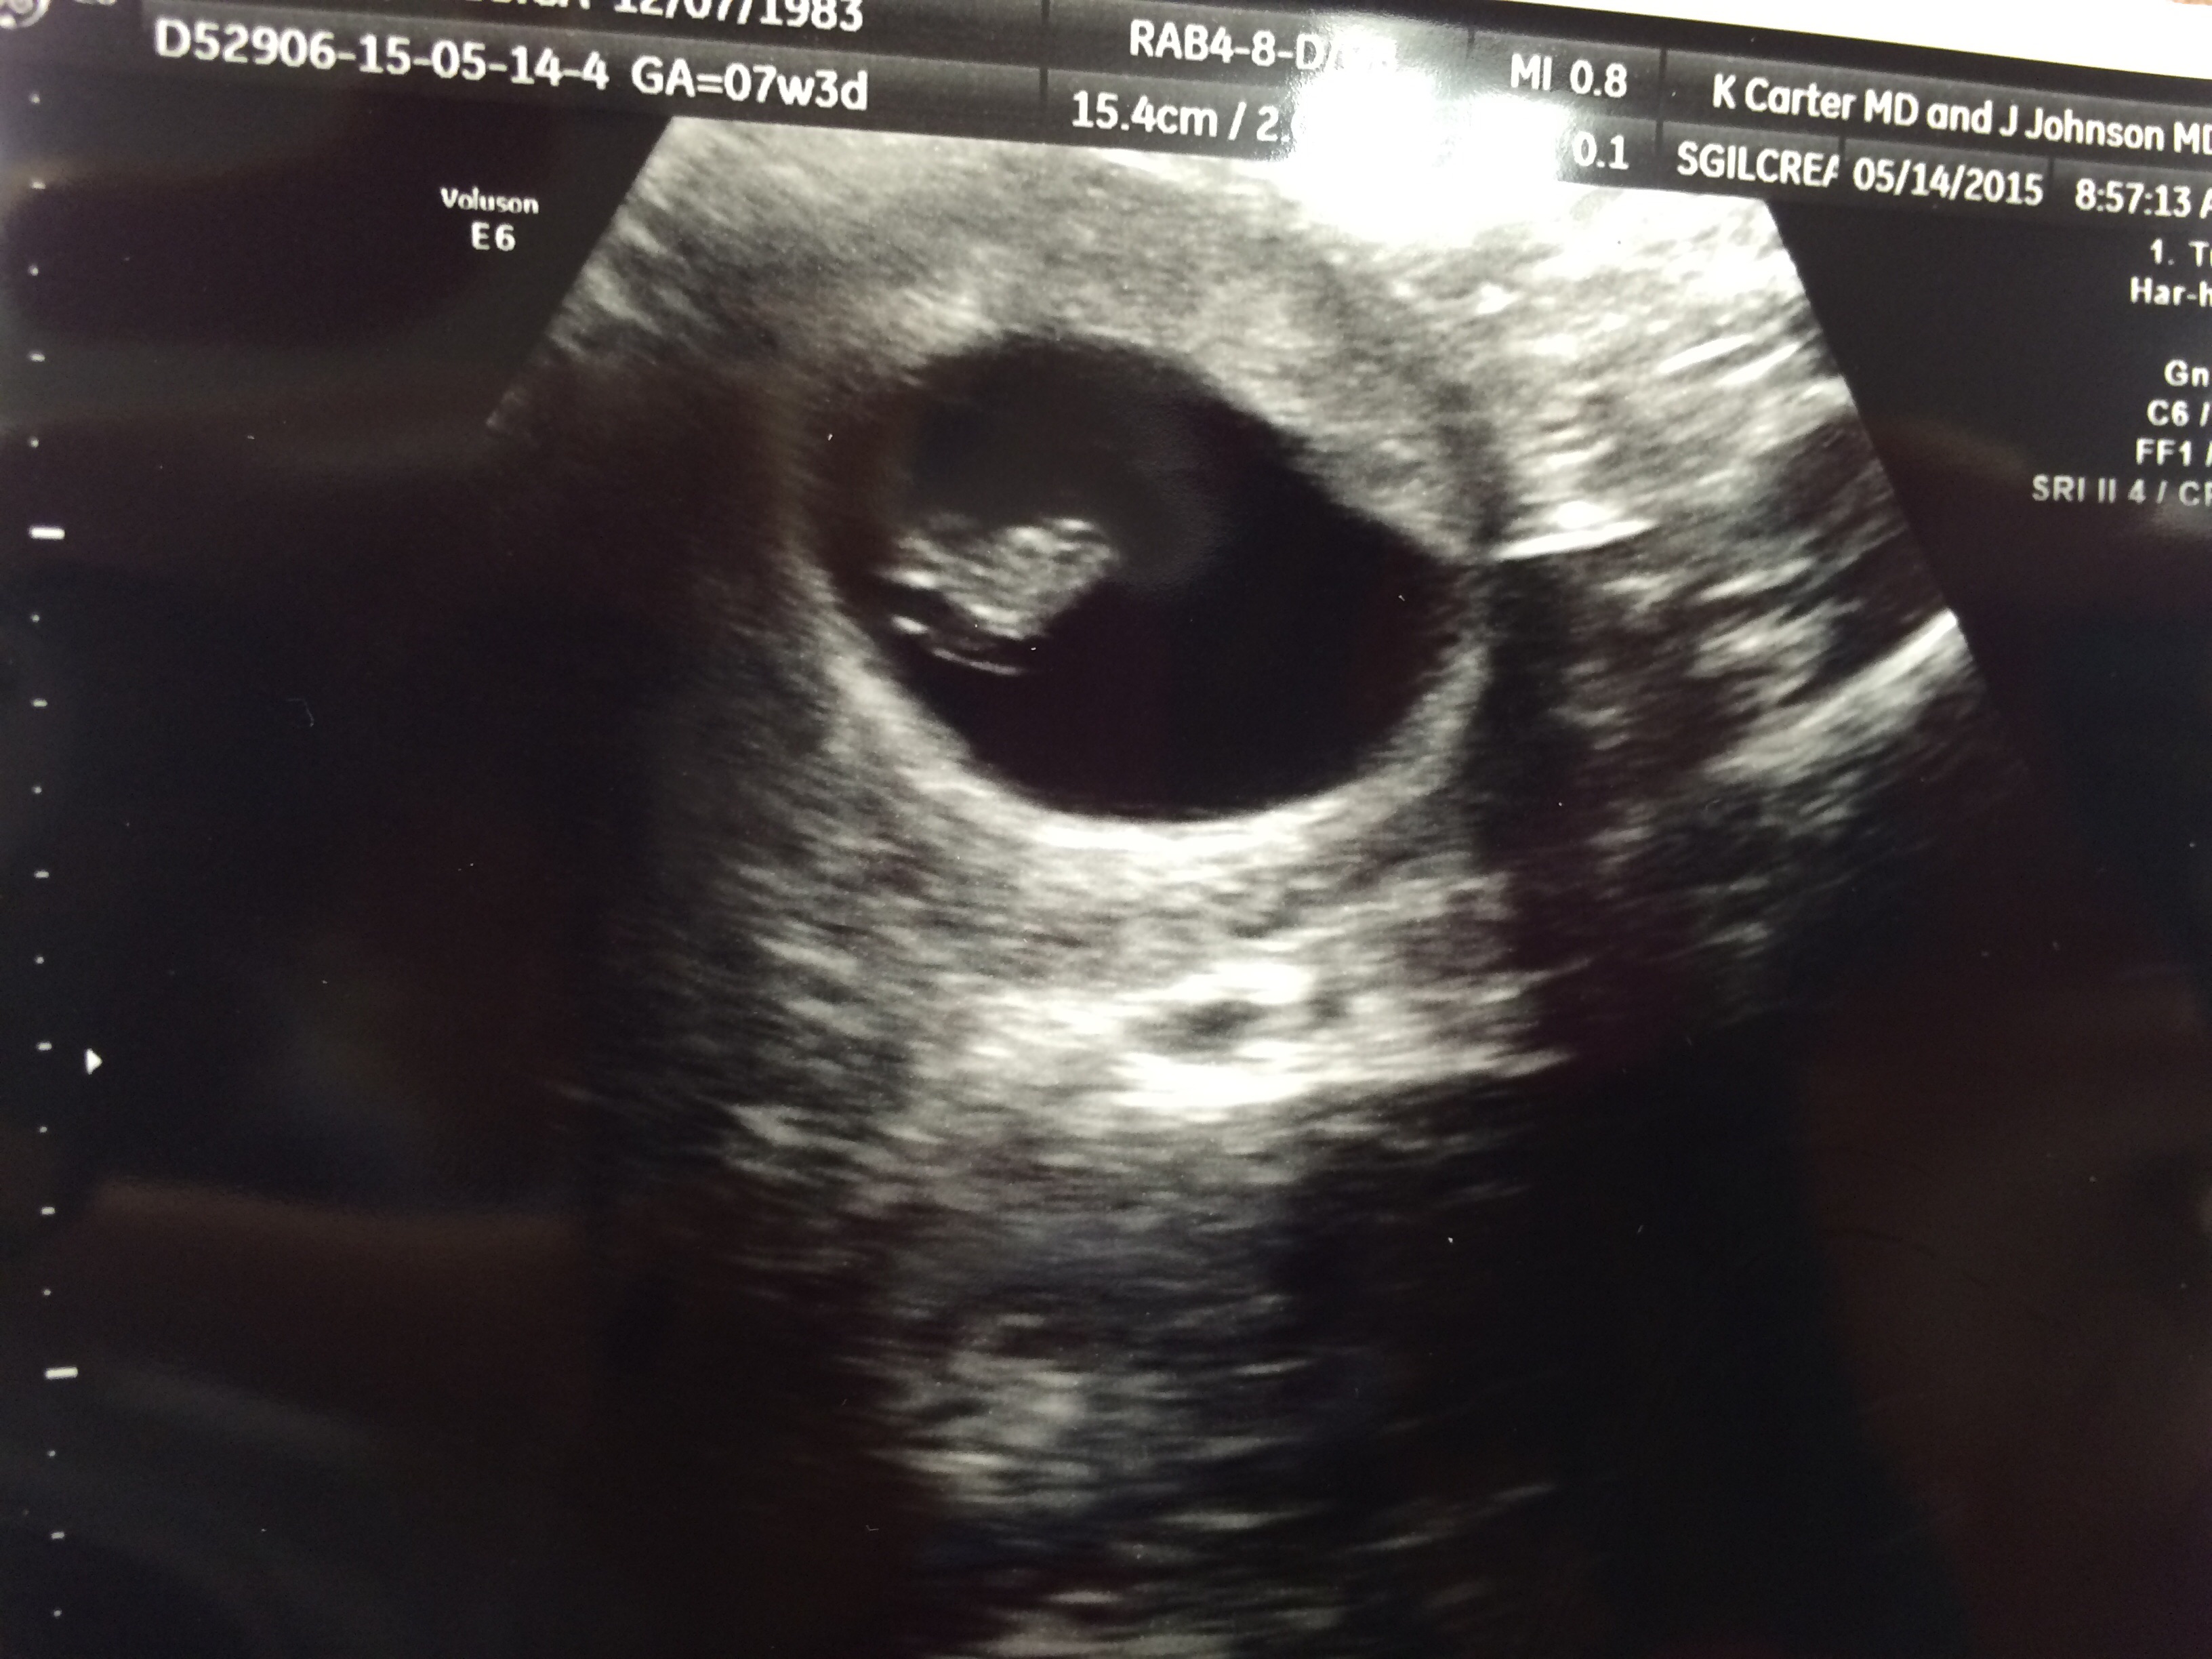

Our little peanut measured 7 weeks 1 day- a few days off, so our new due date is Dec 30. I am still a December birth month yay! Good heartbeat, very relieved and excited!